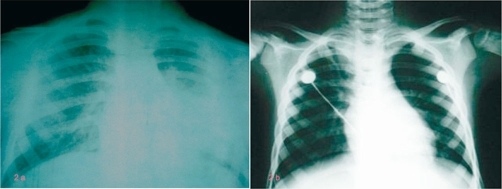

X-ray Croup pra-paska bronkoskopi. Sumber: anonim, Openi, 2009. X-ray Croup pra-paska bronkoskopi. Sumber: Openi, 2009.

Diagnosis croup dapat ditegakkan secara klinis dengan temuan khas berupa batuk menggonggong atau "seal-like barking" cough secara tiba-tiba, stridor inspirasi, suara serak, dan dyspnea yang umumnya memburuk pada malam hari. Pemeriksaan diagnostik tambahan dapat dilakukan jika gambaran klinis atipikal, untuk menyingkirkan diagnosis banding.[1-3]